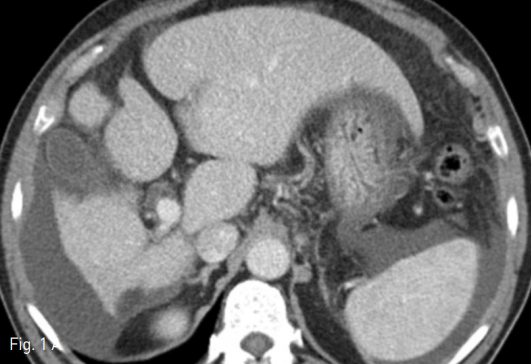

Fig 1A

Contrast enhanced CT scan showed features of chronic liver disease. Axial (A) and coronal (B) images showed hypertrophy of caudate lobe and lateral segments of left lobe with concomitant severe atrophy of the right lobe.

외부병원에서 시행한 컴퓨터 단층촬영(CT)검사에서, 간의 우엽은 심하게 위축되어 있었고 좌측외엽 및 미상엽은 증대되어 있어 만성간염에 합당한 소견이었다(Fig. 1). 이로 인하여 우측 간문맥 역시 매우 위축되어 있었으며, 우간정맥과 우측 간문맥의 거리가 멀어보였다.